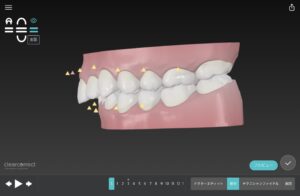

この歯並びの治療計画は

でっ歯さんの度合いを調べる

セファロというレントゲンを撮影

最新のお口のスキャナー

トリウス

歯並びをスキャンして

歯科医が分析

今回は

非抜歯でGo‼️

この歯並びの治し方は

でっ歯

Ⅱ級ゴムで上の歯列を後ろに移動する

えんしんいどう を行う

ディープバイト

上の前歯は上に 下の前歯は下に押し込む

あっか という動き

叢生

歯と歯の間を少し削りスキマを作って

歯をキレイに整列